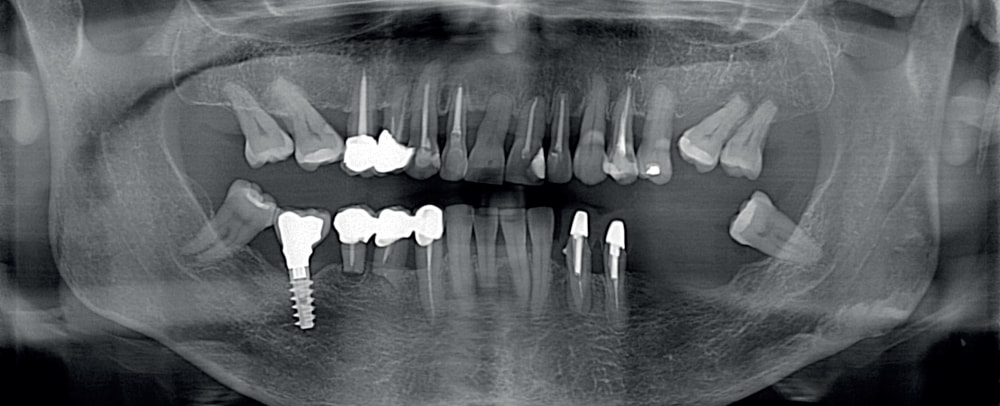

X-MIND® optima jest również zintegrowany z WeDiagnostix – intuicyjnym i ultraszybkim oprogramowaniem AI wspierającym radiologię stomatologiczną.

Sztuczna inteligencja wediagnostix jest wynikiem ciągłych badań i rozwoju oraz sieci neuronowych trenowanych na 90 000 zębów, 81 000 zabiegów, 40 000 patologii. Osiąga wyniki detekcji, które wcześniej nie były możliwe w stomatologii. Na podstawie analizy wczytanych zdjęć:

• w ciągu kilku sekund zaznacza na ekranie patologie zębowe i pozazębowe,

• eliminuje wszelkie błędy interpretacyjne człowieka, wykrywa patologie słabo widoczne gołym okiem lub mogące umknąć uwadze,

• dostarcza gotowy, kompleksowy i zawsze edytowalny raport, gwarantując wyniki zgodne z wymogami prawnymi.

1) Ładowanie zdjęcia pacjenta jednym kliknięciem

Eksport zdjęć rentgenowskich do WeDiagnostix bezpośrednio z oprogramowania do obsługi tomografu lub zarządzania pacjentami.

4) Opis całego zdjęcia rentgenowskiego

Z uwzględnieniem obszarów patologii pozazębowych.

5) Generowanie raportu

Gotowy raport można wyeksportować do oprogramowania do zarządzania pacjentami lub oprogramowania radiologicznego, jak również wygodnie wydrukować lub wysłać do współpracowników/pacjenta.